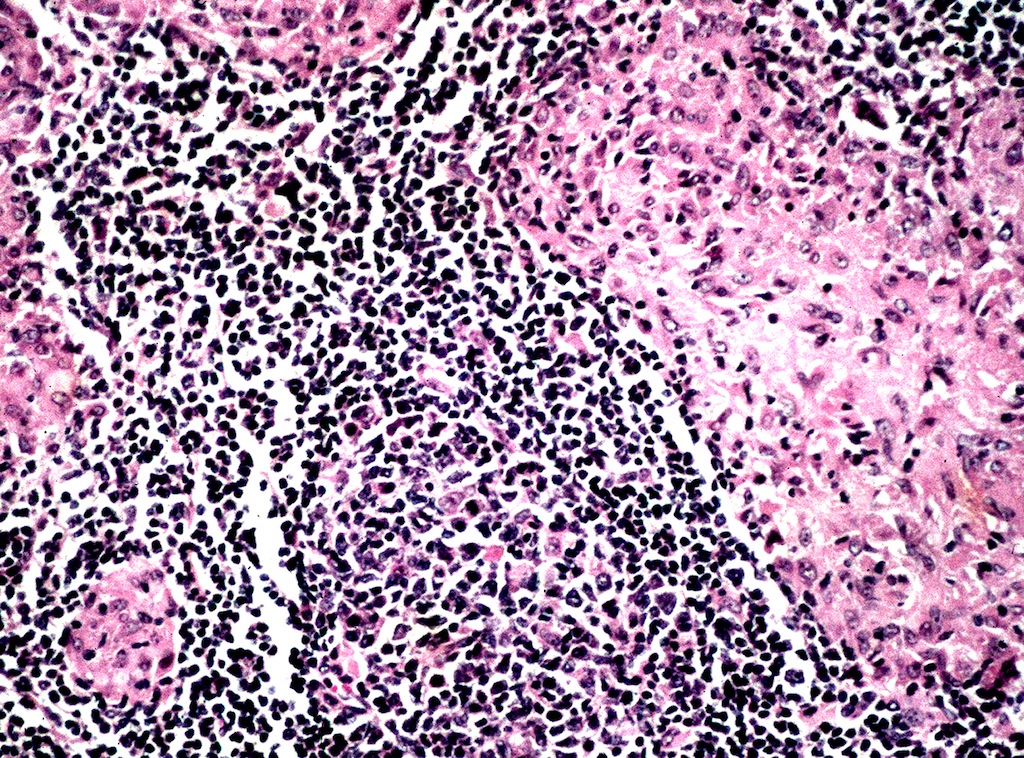

Yersinia pseudotuberculosis

Definition / general

- Clinical picture usually resembles acute appendicitis with possible abdominal mass but laparotomy often shows mesenteric lymphadenitis (Eur J Pediatr Surg 1997;7:180)

Microscopic (histologic) description

- Capsular thickening and edema

- Granulomas with central necrosis and microabscesses

- Immunoblasts and plasma cells in cortical and paracortical region, large lymphocytes within sinuses, germinal center hyperplasia